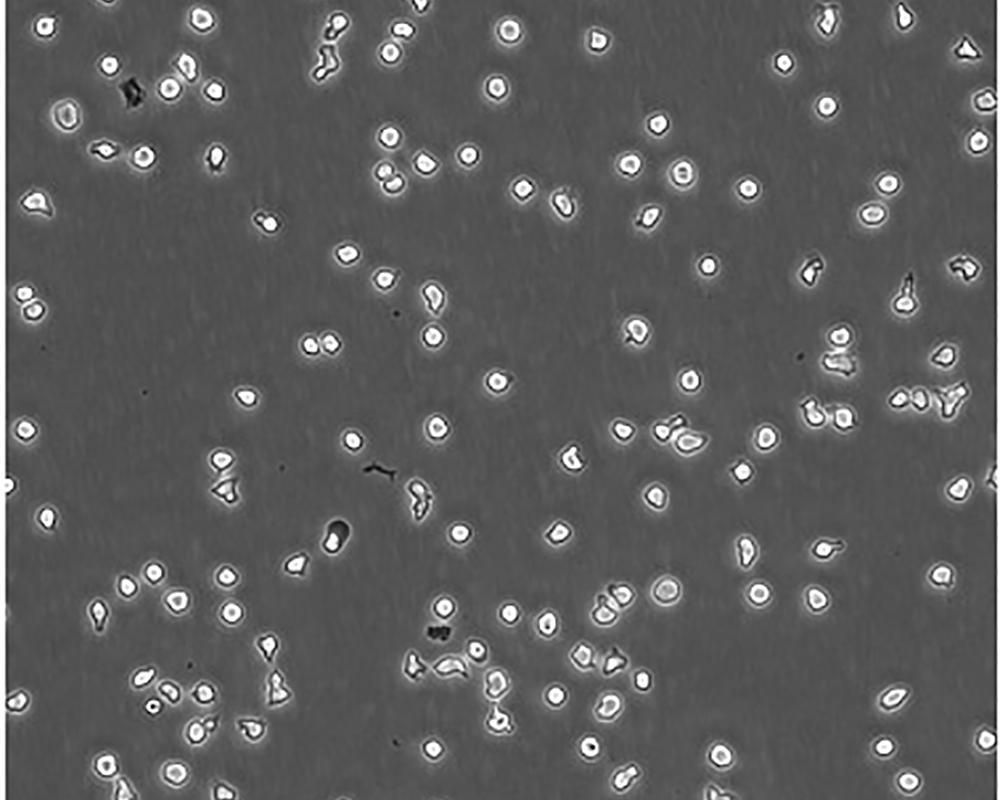

生長特性 suspension

形態特征 lymphoblast

細胞描述 一位套細胞淋巴瘤患者的巨細胞變種顯示白血病轉變,從其外周血單核細胞出發建立了MCL細胞株JeKo-1。 JeKo-1細胞EB病毒陰性,并表達一種B細胞表型的IgM。 細胞過表達cyclin D1, Bcl-2, c-Myc 及 Rb 蛋白。 Bcl-1/J(H)基因重排得到了PCR證實。 JeKo-1細胞在SCID小鼠中高成瘤。 [PubMed: 9753063]